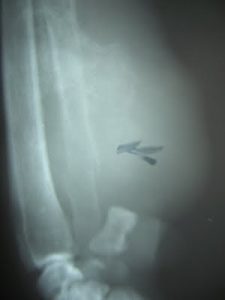

Se recomienda realizar un diagnóstico acompañado de radiografías de la lesión y un estudio histopatológico. Cuando no exista concordancia entre los resultados de el estudio citológico con los resultados del estudio histopatológico la recomendación diagnóstica del autor es guiarse por el resultado de la prueba citológica. El diagnóstico simplemente radiográfico es posible y es materia de los radiólogos y traumatólogos veterinarios.